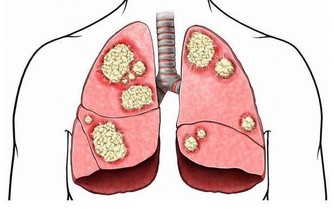

俗話說,傷筋動骨100天。老年人跌倒後通常卧床,或者傷殘肢體制動很長一段時間,

會因為廢用等因素導致肌肉萎縮、骨質疏鬆;

最嚴重的可造成關節攣縮,將嚴重影響肢體功能,降低恢復後老人的活動能力,甚至過早死亡。